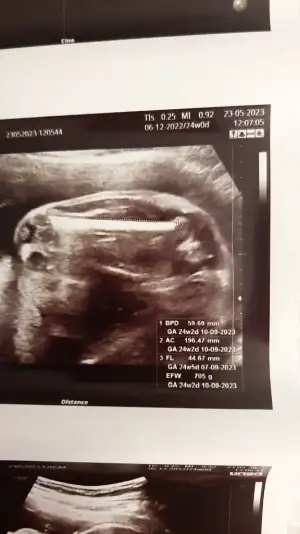

Kızlar ultrason kağıdı ile ilgili bildiklerimi paylaşmak istedim. Çoğumuzda soru işaretleri var belki işinize yarar.

Boy kg önden gitme nedir filan bunları anlatmak için örnek atıyorum.

En üstte son adet tarihi yazıyor. Yanında 24 w 0 d diyor.

(22 hafta 0 günlükmüş son adete göre)

Ama en aşağıda

BPD (baş çapı) 24 hafta 2 gün (yani 2 gün önde)

AC (karın çapı) 24 hafta 2 gün (2 gün önde)

FL (femur uzun.) 24 hafta 5 gün (5 gün önde)

Efw gramı 705 grammış..

GA'da bunlara bakarak bebeğin ortalama kaç günlük olduğu 24 hafta 2 gün çıkıyor yani bunlara bakarak bebek 2 gün önden gidiyor diyor.

Bebeğin boyu için de FL ile 7yi çarpıyoruz. 31.2 cm çıkıyor. :)

Ama bu doktorun işaretlemesiyle alakalı mesela resimde femuru ölmüyor bir tık sağa yada sola işaretledr mm değişiyor. O nedenle doktordan doktora makineden makineye de değişiyor. Bu yüzden 1 hafta ve altı farkları doktorlar normal görüyor söylemiyor bile. Günüyle uyumlu diyor geçiyor.. ama biz anneler önden gidiyor demesi hoşumuza gidiyor🤣🤣